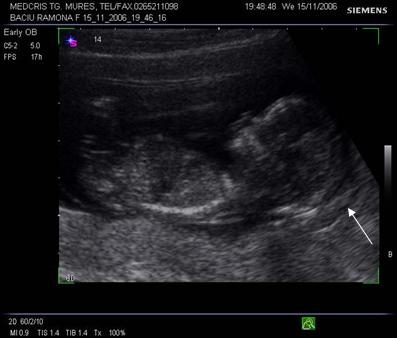

Fig nr 113. Acrania la o sarcina de 11 sapt.(ecografie abdominala ) Linia indica absenta calotei craniene

Fig. nr.114. Calota craniana normala ( cu sageata ) la ecografia abdominala. Se remarca proportia normala intre marimea capului si a fetei, spre deosebire de acrania din figura anterioara